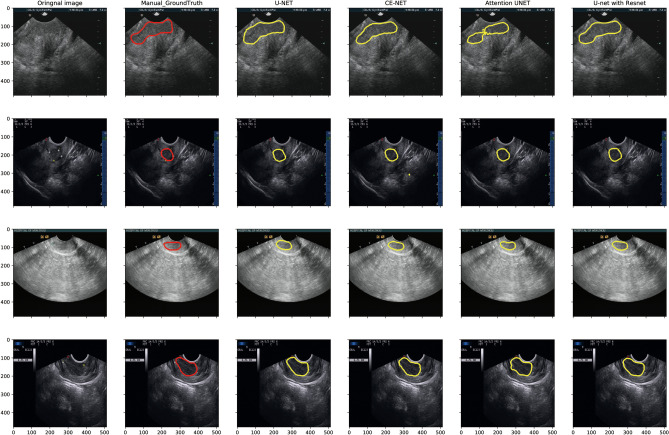

Figure 3 presents typical target area contours achieved by U-net, Attention U-net, CE-net, and U-net with ResNet automatic segmentation models and their comparison with manual contours on US images for cervical cancer, respectively. The training and validation loss, as well as the performance of different models for training and validation cohorts, are shown in Fig. 4.

Fig. 3.

Typical target area delineated by U-net, Attention U-net, CE-net, and U-net with ResNet automatic segmentation models and their comparison with manual contours on ultrasound images for cervical cancer

The differences among different U-net models according to DSC were also analyzed and presented in Fig. 4c by paired T test, in which the numbers were average DSC values resulting from row models minus the column ones with p value shown in different colors. The backbone of U-net is replaced by ResNet consisting U-net with ResNet. CE-net added context extractor block into U-net with ResNet. Attention U-net have Attention block. Compared with U-net, ResNet backbone had a significant improvement in DSC, while CE block and Attention block had no statistically significant improvement, as shown in Fig. 4c. Detailed evaluation of the segmentation performance for different automatic segmentation models is presented in Table 2. The mean DSC of U-net, Attention U-net, CE-net, and U-net with ResNet were 0.88, 0.89, 0.88, and 0.90, respectively.

One limitation of the U-net-based models for US automatic segmentation is that there may be some artifacts resulting from less optimal algorithms as shown in Fig. 3, which will further result in the worse reliability and reproducibility of some shape features, as shown in Fig. 6. The network models used in this paper were probably not good at delineating the cervical tumor boundary, which results in the low reliability and high reproducibility of shape features. Manual corrections may be warranted during clinical practice with these U-net-based automatic segmentations. Another limitation of this study is the only B-model images were investigated. Further studies on radiofrequency and envelope-detected signals of US may be helpful to further verify the accuracy of these automatic segmentations.